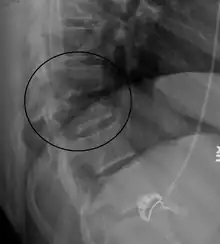

A Chance fracture of T10 and fracture of T9 due to a seatbelt during an MVC. | |

On plain X-ray, a Chance fracture may be suspected if two spinous processes are excessively far apart.[10]